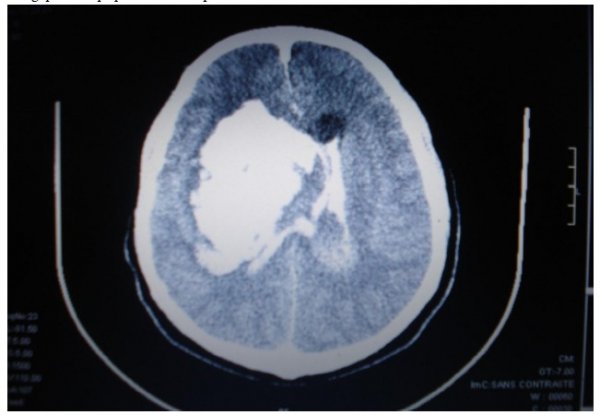

Un homme de 60 ans était admis au service des urgences puis au service de réanimation chirurgicale du CHU Joseph Ravoahangy Andrianavalona, le 24 Juillet 2008, à la suite d’une chute dans un ravin, sans point d’impact précis. Le patient était éthylique, tabagique à 10 paquets années et présentait dans les antécédents une notion de crises convulsives apyrétiques. Il n’avait pas d’antécédents cardiovasculaires ni respiratoires antérieurs. A l’entrée, la pression artérielle était de 140/80 mm Hg, la fréquence cardiaque était à 90 battements par minute, la fréquence respiratoire à 30 cycles par minute et le patient était coloré. La saturation périphérique en oxygène (Sp02) était de 97%. L’examen neurologique avait révélé un score de Glasgow à 8/15, des pupilles en myosis réactives symétriques, un déficit moteur gauche et une raideur de la nuque. Le reste de l’examen était normal. L’hémogramme avait montré une légère anémie normochrome normocytaire, et une hyperleucocytose à prédominance neutrophile. L’ionogramme sanguin et le reste de l’examen sanguin étaient normaux. La tomodensitométrie cérébrale effectuée en urgence avait objectivé une volumineuse hémorragie intracérébrale droite avec oedème péri lésionnel compliquée d’une hémorragie sous-arachnoïdienne et d’une inondation intra ventriculaire. On notait également une fracture multi fragmentaire de la paroi du sinus maxillaire droit. (figure1)